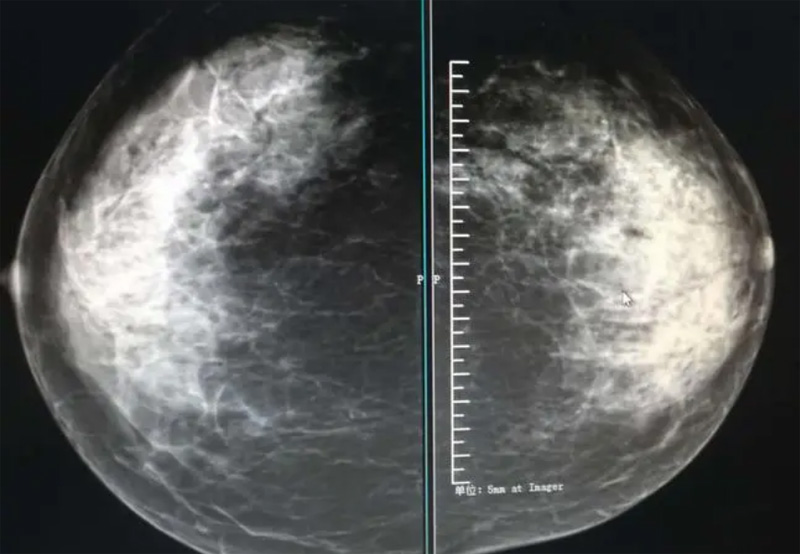

乳腺DR攝影體位有頭尾位及內(nèi)外側(cè)斜位,

乳房在片子的中央,乳頭切線位,可見小部分胸大肌,內(nèi)側(cè)乳腺組織應(yīng)全部包括在片中,外側(cè)乳腺組織盡可能包括在片中。一張好的MLO位圖像顯示如下:乳房被推向前上,乳腺實(shí)質(zhì)充分展開,胸大肌可見,較松弛,下緣達(dá)到乳頭水平,乳頭在切線位,部分腹壁包括在片中,但與下部乳腺分開,絕大部分乳腺實(shí)質(zhì)顯示在片中。乳腺組織外緣可見乳頭的輪廓;乳腺后方的脂肪組織被很好地顯示出來,乳房無皺褶。對(duì)于CC位及MLO位顯示不良或未包全的乳腺實(shí)質(zhì),可以根據(jù)病灶位置的不同選擇以下體位:外內(nèi)側(cè)位(LM)、內(nèi)外側(cè)位(ML)、內(nèi)側(cè)頭尾軸位(MCC)、外側(cè)頭尾軸位(LCC),尾葉位(CLEO)及乳溝位。在臨床實(shí)踐中,對(duì)于常規(guī)體位上發(fā)現(xiàn)的異常改變,可以進(jìn)一步采取一些特殊的攝影技術(shù),包括局部加壓攝影、放大攝影或局部加壓放大攝影技術(shù)。

必須指出的是,美國(guó)放射學(xué)會(huì)提出的乳腺影像報(bào)告和數(shù)據(jù)系統(tǒng)(Breast Imaging Reporting and Data System, BI-RADS)將乳腺分為4型:脂肪型(乳腺內(nèi)幾乎全部為脂肪組織,腺體組織占25%以下)、少量腺體型(乳腺內(nèi)散在腺體組織,大約占25%~50%)、多量腺體型(乳腺呈不均勻致密表現(xiàn),腺體組織大約占51%~75%)、致密型(乳腺組織非常致密,腺體組織占75%以上)。這種分型的主要意義在于說明X線對(duì)不同乳腺類型中病變檢出的敏感性不同,對(duì)發(fā)生在脂肪型乳腺中病變的檢出率很高,而對(duì)發(fā)生在致密型乳腺中病變的檢出率則有所降低,臨床醫(yī)師了解這一點(diǎn)很重要。